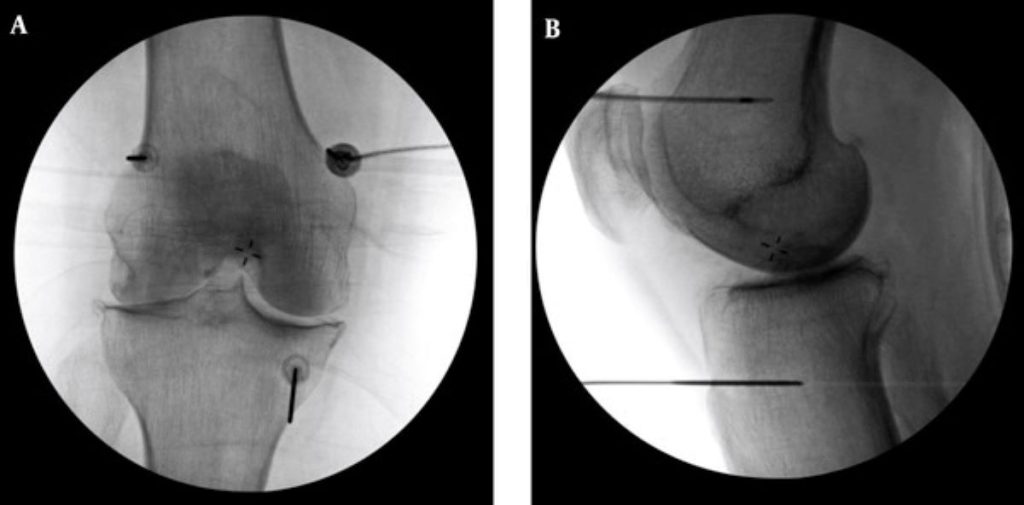

李宜軒說明,此項技術過往多用於椎間盤突出、滑脫等脊椎神經壓迫造成的下背痛、坐骨神經痛的止痛治療,近來也運用至膝關節退化。執行方式是在局部麻醉的情況下,以X光定位將電極導針導引至膝蓋的三個主要感覺神經叢,確認施行目標後,接上電源線輸出高頻電波,藉由熱能與電效應,使引起疼痛的神經失去傳導疼痛的能力,降低疼痛。

為確保施行過程中未傷及運動神經,治療前會進行不同電量測試,並請病人活動膝蓋,在確定不影響日後活動的情況下進行治療。一般而言,效果會在術後當下至一週內顯現,普遍可維持半年至一到兩年,因人而異。